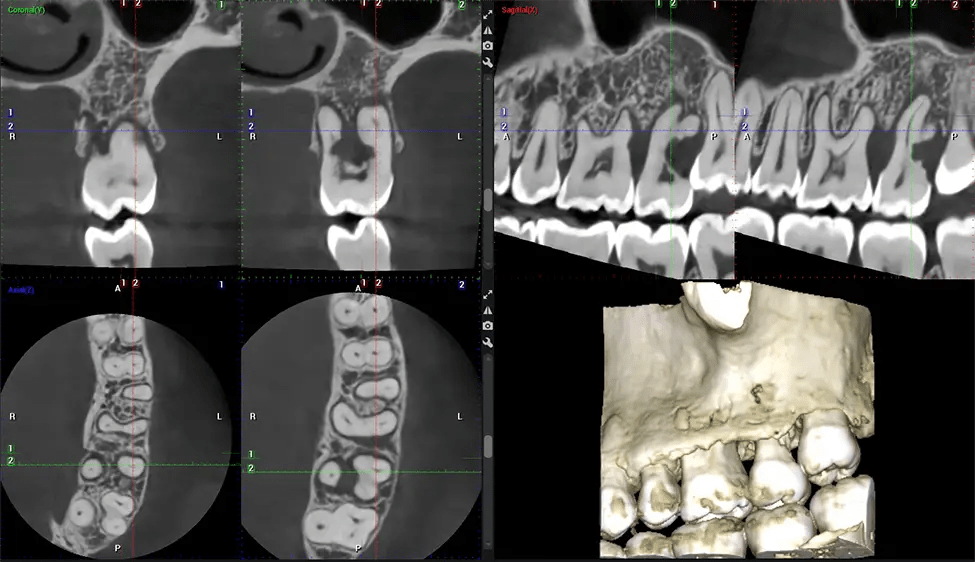

Tomografía computarizada de haz cónico (CBCT) es una técnica de imagen avanzada utilizada en odontología y cirugía maxilofacial para obtener imágenes 3D detalladas de las estructuras orales y maxilofaciales. Dr. G Estudio Dental, nuestro CBCT Los escáneres utilizan un haz de rayos X en forma de cono y un detector especializado para capturar imágenes desde diferentes ángulos. Posteriormente, una computadora combina estas imágenes para crear una representación tridimensional de la anatomía oral del paciente.

Esta exploración 3D, llamada tomografía computarizada de haz cónico, le brinda a su dentista una imagen más completa de su anatomía bucal y sus procesos patológicos que una radiografía tradicional. A diferencia de las radiografías convencionales, que capturan una imagen 2D de la boca desde varios ángulos, una exploración 3D toma varias radiografías digitales para una imagen. Proporciona una vista completa de la mandíbula, los dientes, los nervios y los tejidos blandos. Esta vista mejorada permite a los dentistas detectar problemas menores que no son visibles en las exploraciones 2D tradicionales, como muelas del juicio impactadas o fracturas óseas en la cavidad sinusal.

Después del proceso de escaneo, las imágenes de rayos X capturadas son procesadas por el CBCT software, que aplica algoritmos para reconstruir una imagen 3D detallada del área escaneada. El software compila estas imágenes de rayos X individuales y crea una representación digital 3D de la anatomía del paciente. La 3D reconstruida CBCT La imagen puede ser visualizada y analizada por el dentista o el radiólogo. Esta imagen puede manipularse, rotarse y ampliarse o reducirse para examinar estructuras específicas y evaluar el estado del paciente.